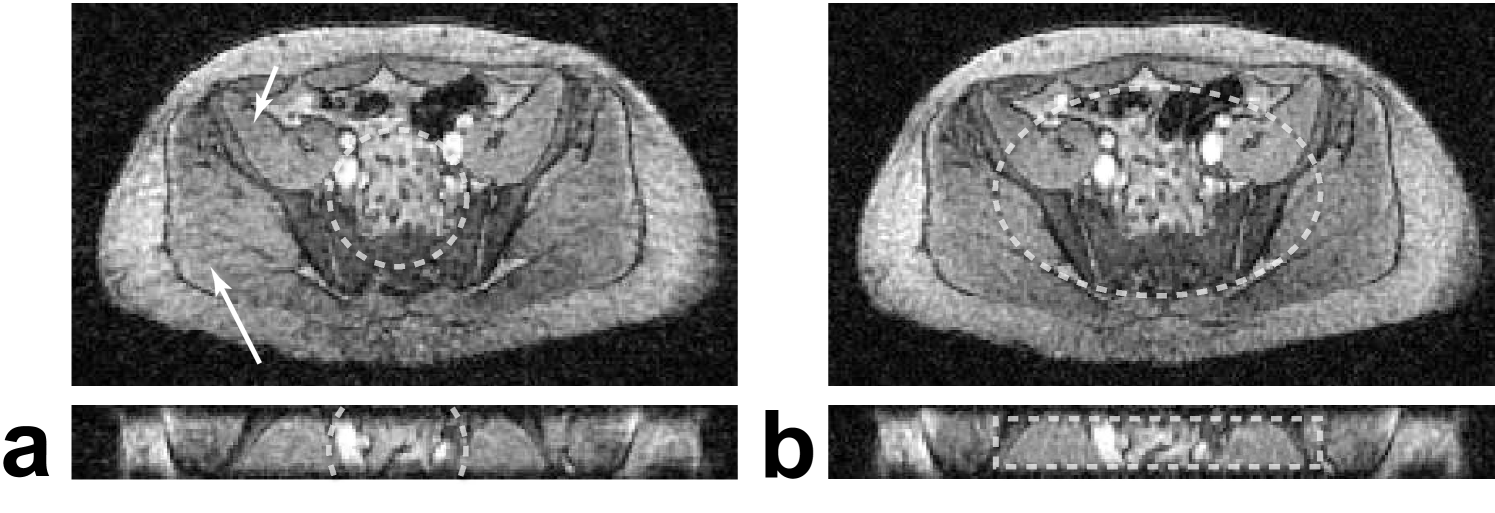

Refer to caption

Figure 13: 3D PR phantom images, all acquired with the same number of projections. Isotropic FOV using the (a) cones-based method and (b) spiral-based method. Cylindrical FOV using the (c) cones-based method and (d) spiral-based method. The top images are all windowed identically to show the aliasing artifacts outside the bottle (white arrows). The bottom images are also identically windowed to show the aliasing artifacts within the bottle for the undersampled, isotropic FOVs (black arrows). The dashed lines indicate the supported FOV.

Figure 13 shows a representative slice from 3D PR acquisitions of a water bottle phantom using different FOVs, each with the same number of projections. In the isotropic FOV acquisitions, streaking artifacts are visible within the bottle and emanate from the edge of the bottle (arrows in Fig. 13a and b) because the FOV is not large enough. These artifacts have a peak amplitude of 23.2% of the signal for the cones-based design and 11.5% for the spiral-based design. By using a fully-sampled cylindrical FOV that matches the bottle’s shape, these streaks are completely shifted outside of the bottle. (arrows in Fig. 13c and d). The differences in aliasing diffusivity between the two 3D PR design methods, shown in the PSFs in Fig. 10, can also be seen in the images. There is a single, prominent aliasing streak when using the cones-based design (long, thin arrows), which is diffused with the spiral-based design (short, fat arrows), and the peak aliasing amplitudes also reflect this difference.

Figure 14: Axial (top) and coronal (bottom) slices from a thin-slab 3D PR abdomen data-set with 3 mm isotropic resolution acquired in a single breath-hold. (a) Isotropic 11.4 cm FOV requiring 2303 projections. (b) Cylindrical 36 x 23 x 3 cm FOV requiring 2368 projections. Both trajectories were designed using the spiral-based method. Streaking artifacts result from the high axial undersampling of the isotropic FOV (arrows in (a)). The tailored FOV eliminates these artifacts by reducing FOV in the slab dimension. This leads to the streaks in the coronal slice (arrows in (b)), but these are outside of the imaging volume.

Figure 15: Same as Fig. 14, except with 2 mm isotropic resolution and increased undersampling. (a) Isotropic 8 cm FOV requiring 2519 projections. (b) Cylindrical 19.6 x 12.2 x 2.8 cm FOV requiring 2529 projections. The undersampled cylindrical FOV has no noticeable streaking artifacts (arrows), which obscure the anatomy with the isotropic FOV.